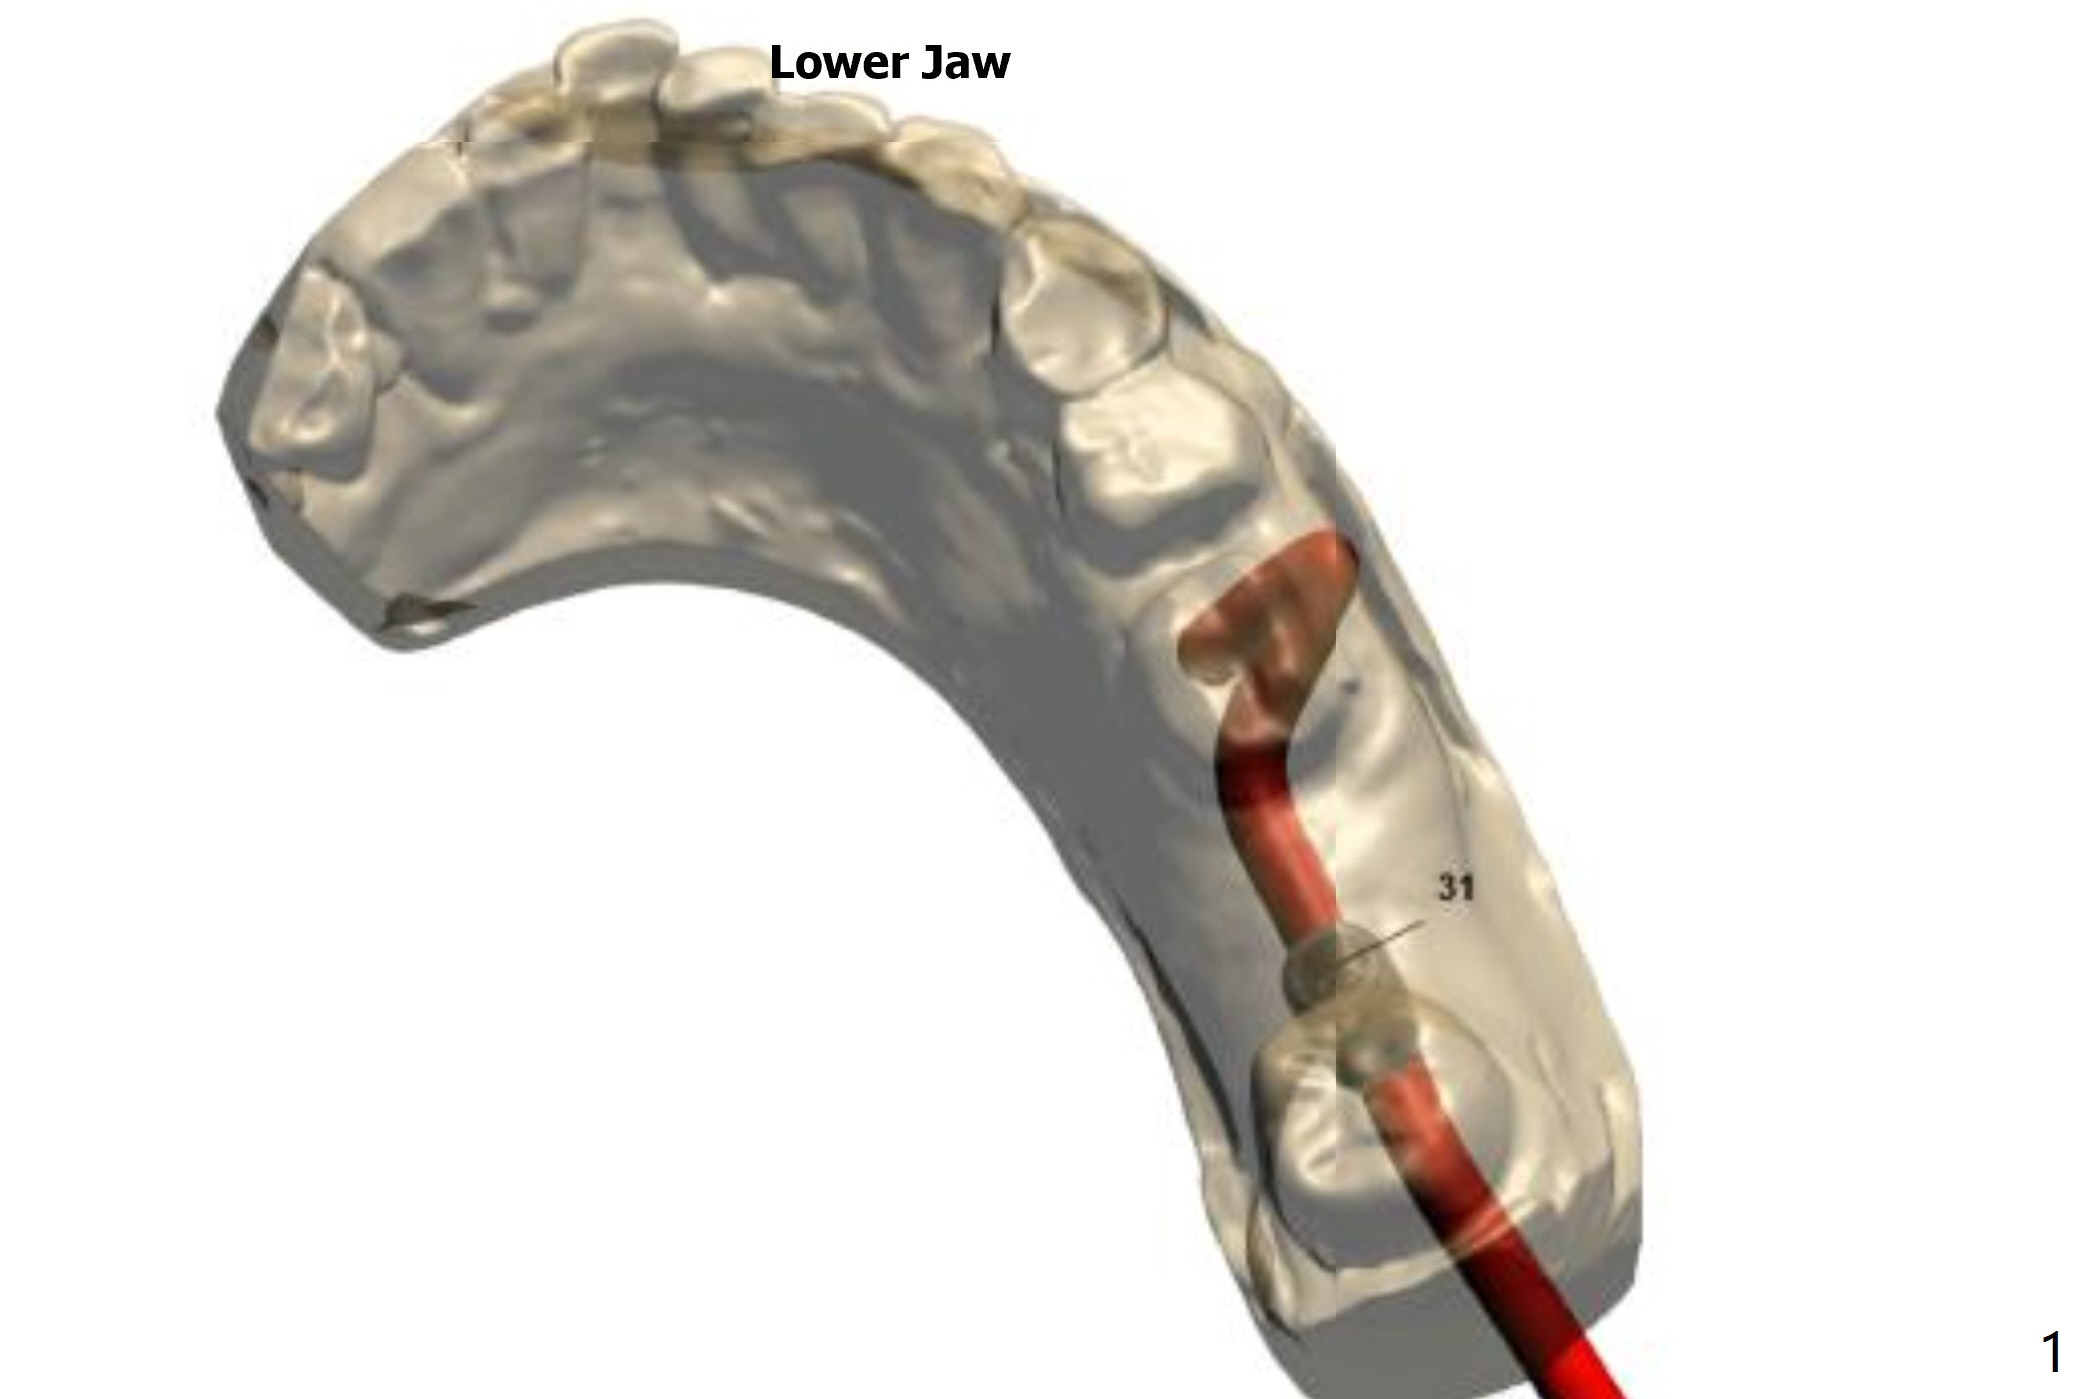

Crestal Level

The distal crest is lower than the mesial one. The 5x10 mm implant is level with the distal crest (Fig.2).